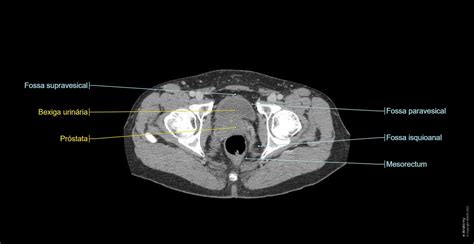

Aressonânciamagnéticadapelveé um exame indolor que possibilita a visualizaçãodeestruturas anatômicas como ossos e músculos sem necessidadedeprocedimentos cirúrgicos e, portanto, menos invasiva. O procedimento estuda as estruturas anatômicas que compõem apelve, como o útero (nas mulheres), a próstata (nos homens), a bexiga, o cólon e o reto, além dos músculos e ossos

Abdômen - Pelve : anatomia normal | e-Anatomy